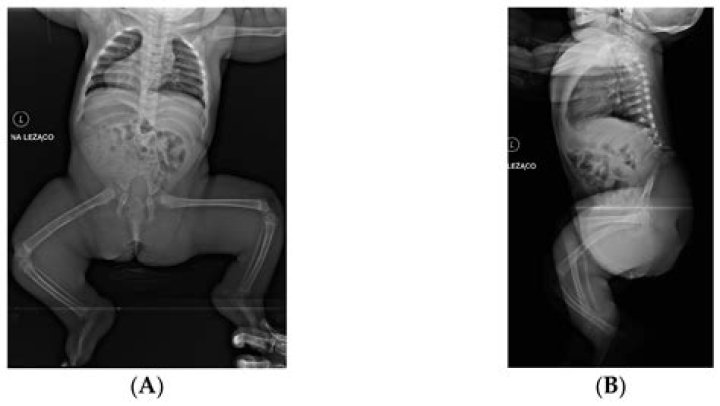

Caudal relapse condition, in some cases sacral agenesis (or hypoplasia of the sacrum), is a profoundly unprecedented birth irregularity. It is an inborn condition wherein there is an irregularity in the development of the caudal segment of the spine during fetal improvement of the lower spine. One occasion of this condition is assessed for each 60,000 live births.